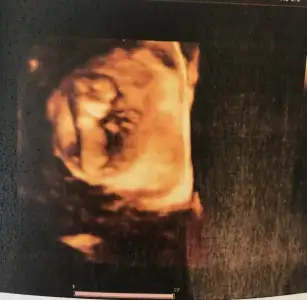

Kızlar herkes haber beklediği için giremedim yazamadım 11+4 çıktı 1 gün önde çıktı yine burun kemiği görüldü ense kalınlığı iyi çıktı sadece küçük olduğu için beyin kemiklerini iyi göremedi onun için haftaya tekrar çağırdı inşllah Ordan birşey çıkmaz iğneyi bıraktırdı fitille haftaya kadar tekrar devam Et dedi haftaya onuda bıraktıra bilir folik asiti bıraktırdı. vitaminlere başladık ocean d vitamini ve balık yağı başlattı Kısaca böyle Kızlar kızçemin fotoğrafını koyayım teyzeleri vitaminlerinde fotoğrafını attım

Kızlar bende geldim 😊 cinsiyet öğrenemedik doktor söylemedi bu haftada belli olmaz bacak arası şimdi baksan boş kız derler buna ama daha anca oluşacak dedi bana sorarsanız kız o kız 😂 ilaçlar aynen devam benim birtek iğne haftada 1 e çıktı 3 hafta sonra belki onuda keser. Ense kalınlığı 1.4 çıktı şükür oda iyi. Fetal DNA testi için kan verdim 15 güne çıkarmış sonuç 2 Li test yaptırmadım o yüzden. Bizim bebişte bu teyzeleri